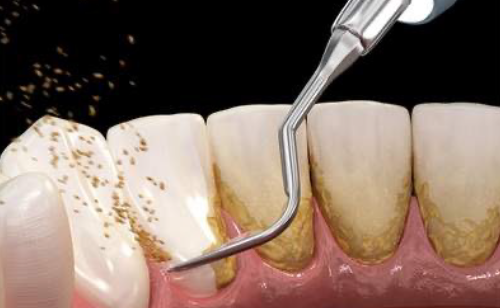

一度ついてしまった着色(コーヒー・紅茶・タバコによる色素沈着)は歯ブラシでは落とすことが困難です。

専用の器具とペーストを使い、できる限り低侵襲で歯の表面のバイオフィルムや着色を除去し見た目も綺麗で汚れの付きづらい状態へと仕上げます。歯の表面がツルツルになり爽快感も得られます。

歯石除去・PMTC(着色と細菌膜の除去)

歯ブラシで落としきれない汚れをプロフェッショナルクリーニングで落とし清潔な口腔内を維持できます。